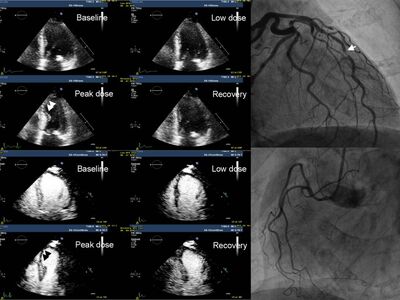

Φαρμακευτική δοκιμασία stress echo με δοβουταμίνη.

Στις εικόνες A και Β στην υπερηχογραφική απεικόνιση και με χρήση παράγοντα ηχοαντίθεσης αντίστοιχα, αποκαλύπτεται περιοχή μειωμένης συσταλτικότητας (βέλος) στη μέγιστη δόση.

Οι εικόνες C και D δείχνουν την επεμβατική στεφανιογραφία του συγκεκριμένου ασθενούς, με σημαντική απόφραξη στον πρόσθιο κατιόντα κλάδο (βέλος).